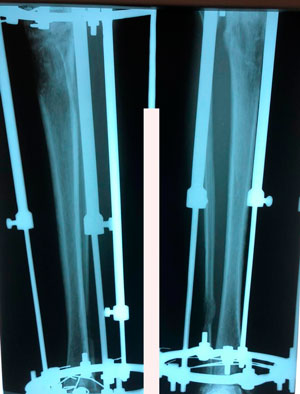

Исходник - 24 года.

Диагноз: врождённое укорочение правой голени на 4 см.

Дата операции - 10.07.2019г.

Костный регенерат в динамике, в процессе удлинения.